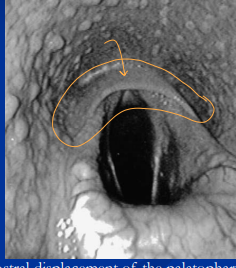

Dynamic DDSP (soft palate)

Sig: 2-3y racehorses

Cs: acute obstruction + “choking down ” at speed,

Dt: treadmill/overground endoscopy

Tx: fitness, tongue tie, myotenectomy, partial staphylectomy

Left laryngeal hemiplegia (“roaring”)

Et: left recurrent laryngeal nerve failure, QHs/Tbs/Drafts

Cs: inspiratory noise + exercise intolerance

Dt: Endoscopy

Tx: prosthetic laryngoplasty “tieback” (Good return to full performance)